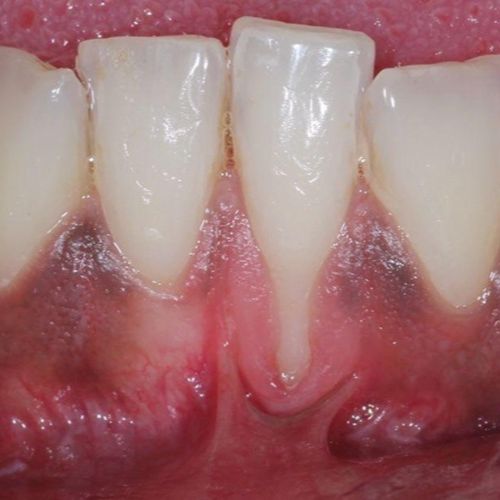

![]() | ![]() |

| Untreated severe gum disease | Gum disease treated and stabilised by Dr Halai |